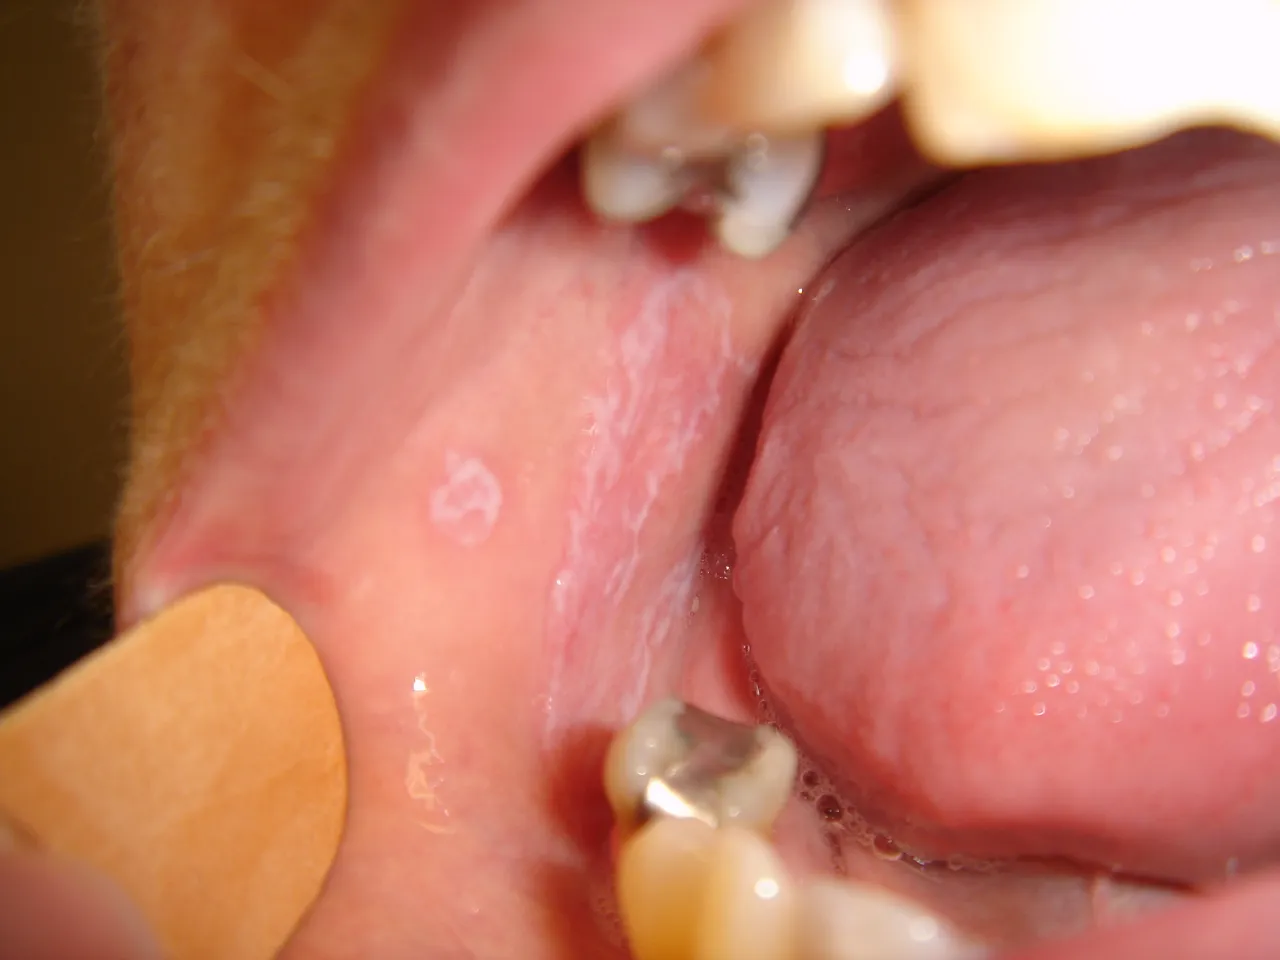

- Charakterystyka: Najczęściej spotykana jest postać siateczkowa, objawiająca się jako białe, koronkowe linie na błonie śluzowej, zwane siateczką Wickhama. Zazwyczaj pojawiają się one na wewnętrznej stronie policzków, ale mogą występować również na języku, dziąsłach czy podniebieniu.

- Inne formy: Oprócz postaci siateczkowej wyróżniamy także postać nadżerkową (charakteryzującą się bolesnymi owrzodzeniami), zanikową (czerwone, gładkie plamy) oraz pęcherzową.